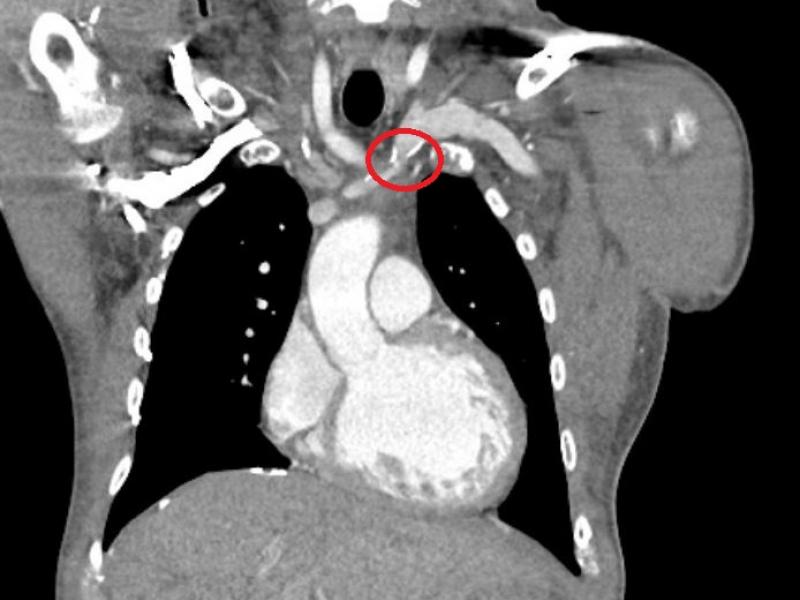

Thoracic Central Venous Obstruction : Stenosis , obstruction